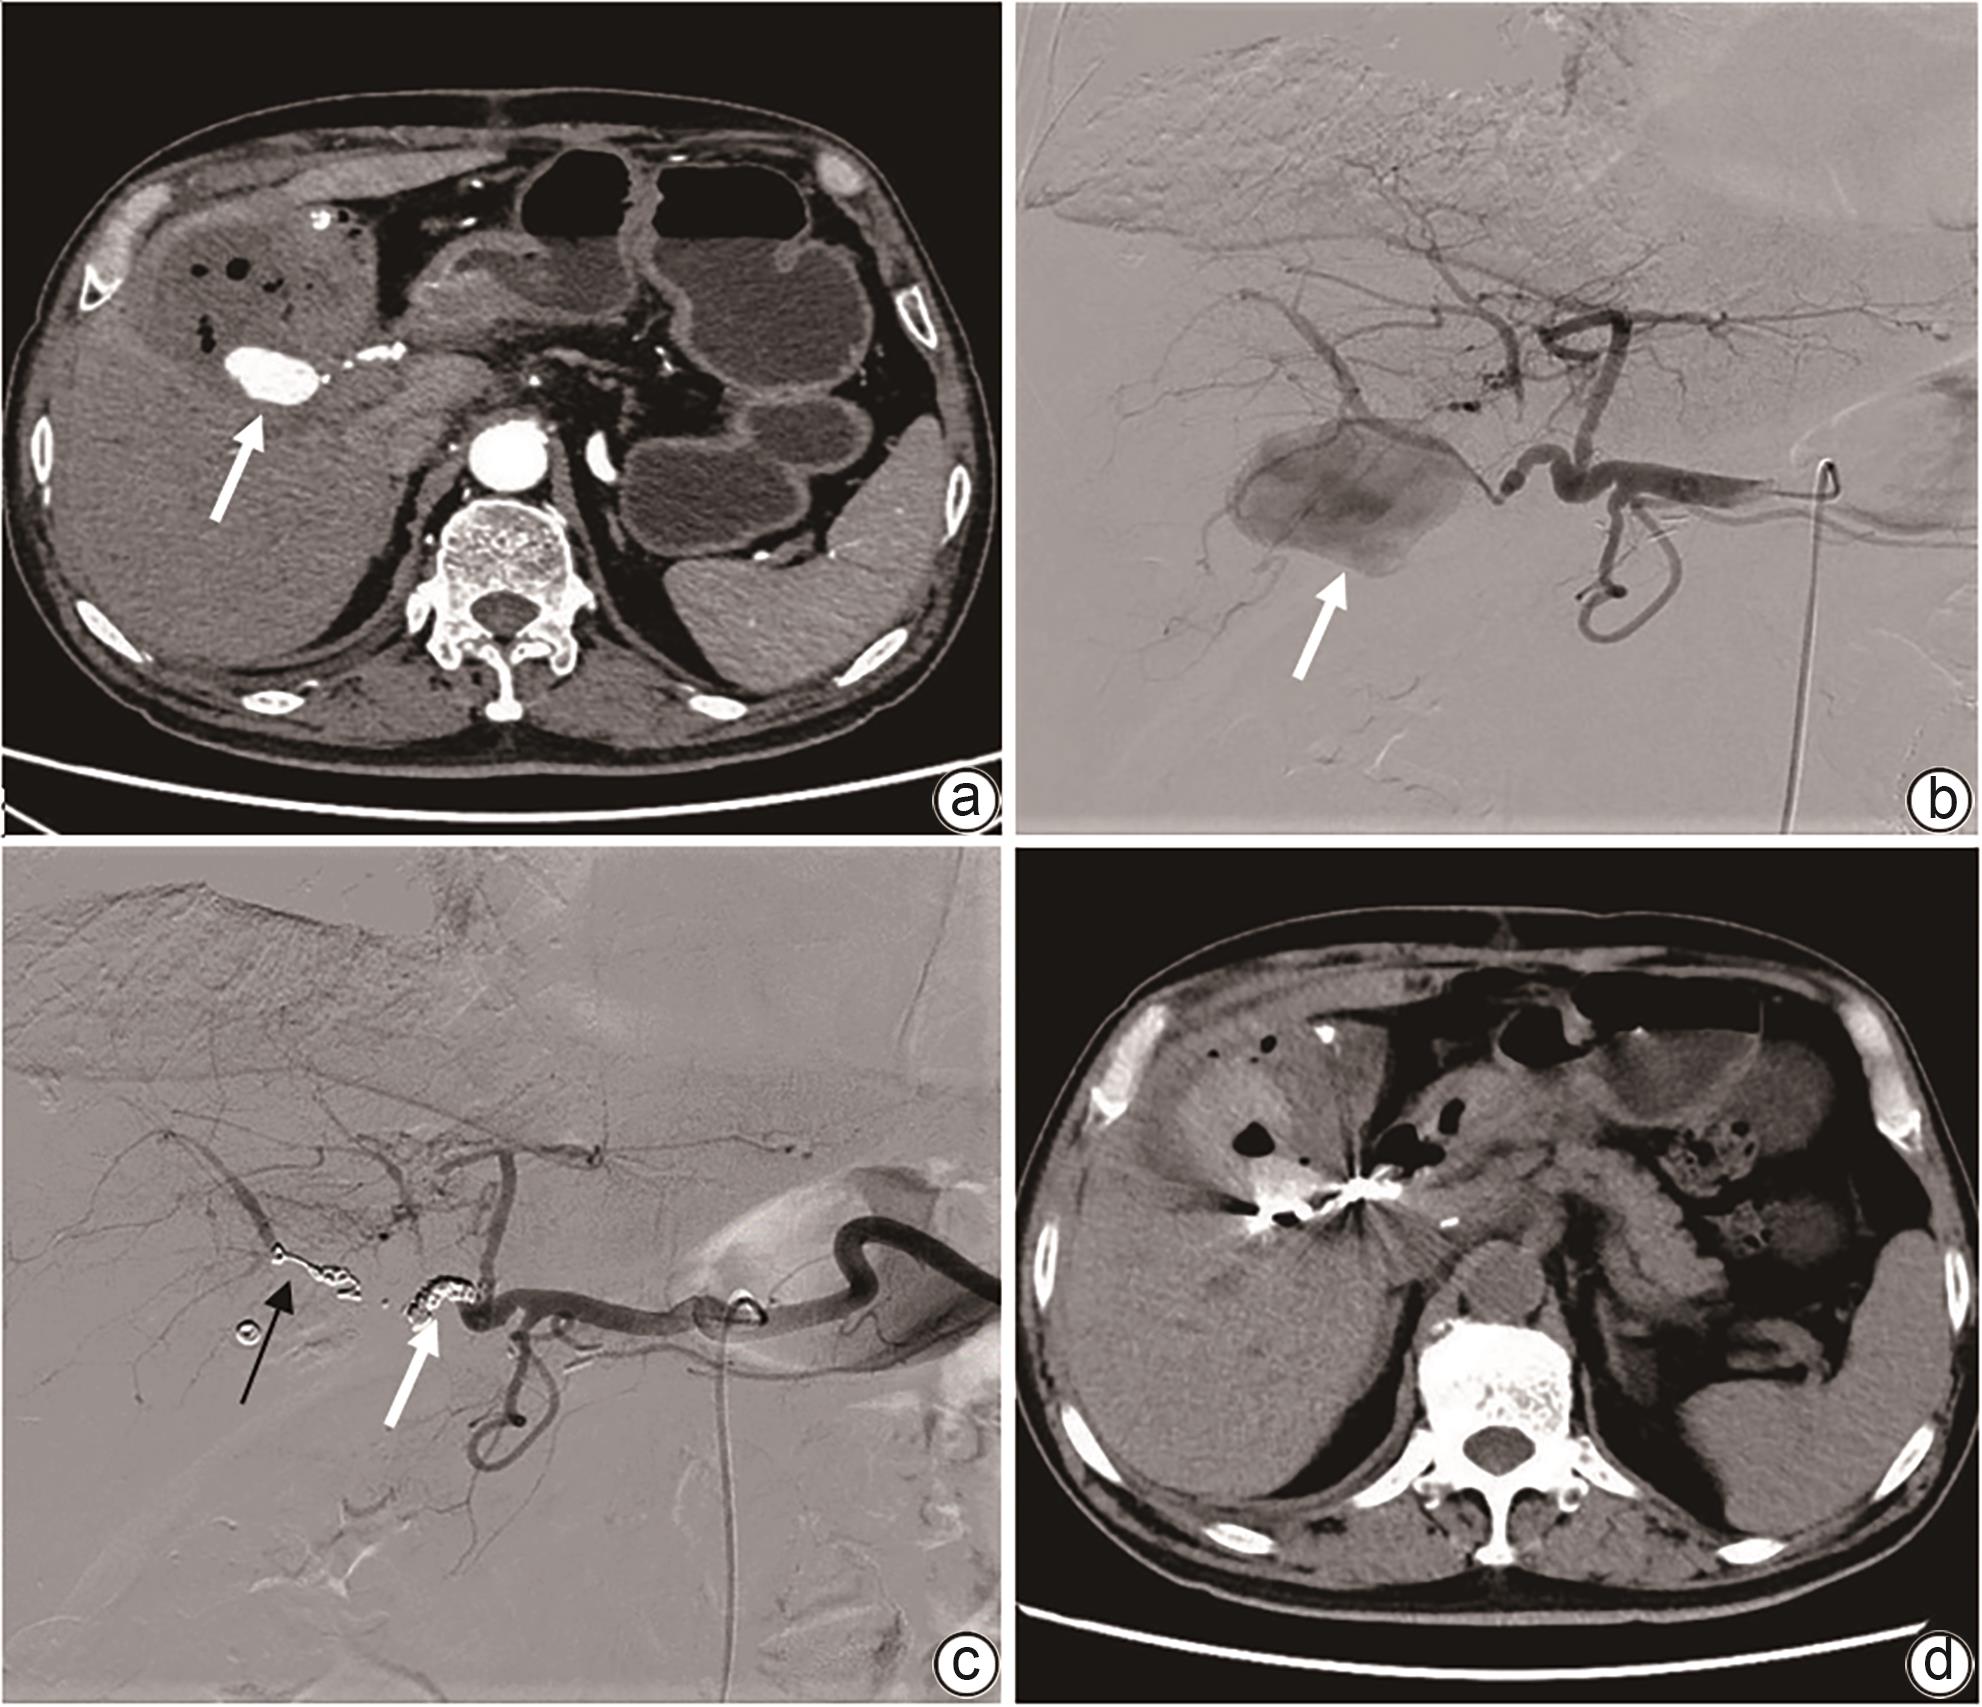

Imaging features and therapeutic strategies for lethal iatrogenic hemobilia

Chen WANG, Min WANG, Ke ZHANG, Jinxing ZHANG, Li LIU, Zhining FAN

2024, 40(10): 2070-2074. DOI: 10.12449/JCH241022

Abstract(997) HTML (354) PDF (2026KB)(80)

Abstract:

Objective  To investigate the imaging features and pathogenesis of lethal iatrogenic hemobilia (LIH) and the value of transarterial intervention in the treatment of LIH.  Methods  A total of 269 patients with upper gastrointestinal bleeding who were admitted to The First Affiliated Hospital of Nanjing Medical University from August 2009 to July 2023 were enrolled, among whom 24 had a confirmed diagnosis of LIH and received treatment, and a retrospective analysis was performed for the clinical data of these 24 patients, including the iatrogenic causes, angiographic findings, and arterial interventions of LIH. Among the 24 patients, 23 received transarterial embolization (TAE) with gelatin sponge particles and coils, and 1 received a covered stent for isolation. The main criteria for assessing treatment outcome included the technical success rate of surgery, procedure-related complications, and long-term clinical follow-up.  Results  Among the 24 patients with LIH, 12 had LIH caused by interventional procedures, and 12 had LIH caused by hepatobiliary and pancreatic surgery. The main clinical manifestations included a significant reduction in blood pressure or a persistent reduction in hemoglobin in 13 patients and upper gastrointestinal bleeding in 18 patients. Among the 24 patients, 2 developed symptoms during surgery, 4 developed symptoms within 24 hours, and 18 developed symptoms after 24 hours. Angiography showed a positive bleeding rate of 100% (24/24), and imaging findings included pseudoaneurysms in 15 patients, hepatic artery truncation in 3 patients, extravasation of contrast medium in 5 patients, and hepatic arteriobiliary fistula in 3 patients. Among the 24 patients, 23 received TAE and 1 received stent implantation. Successful hemostasis was achieved for 23 patients, with a technical success rate of 95.8% (23/24). Four patients developed hepatic necrosis and abscess after TAE, and there was no rebleeding or recurrence after hemostatic treatment.  Conclusion  Various iatrogenic injuries may result in LIH with diverse clinical and imaging findings, and integrated diagnostic imaging combined with transarterial intervention is the best effective life-saving measure for LIH.